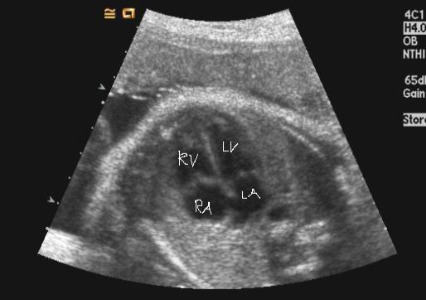

아유, 여기 심장에 작은 구멍이 하나 있네요.

“심장에 작은 구멍이 있는데, VSD(심실중격결손)예요. 아빠도 잘 알겠지만 금방 메워지고 하는 거니까, 걱정하지 말아요. 그래도 혹시 모르니까 대학병원에 가서 심장 초음파는 한 번 받아 보시고요.”

“구멍 크기가 크지도, 작지도 않은데, 일단은 그래도 혹시 모르니까.”